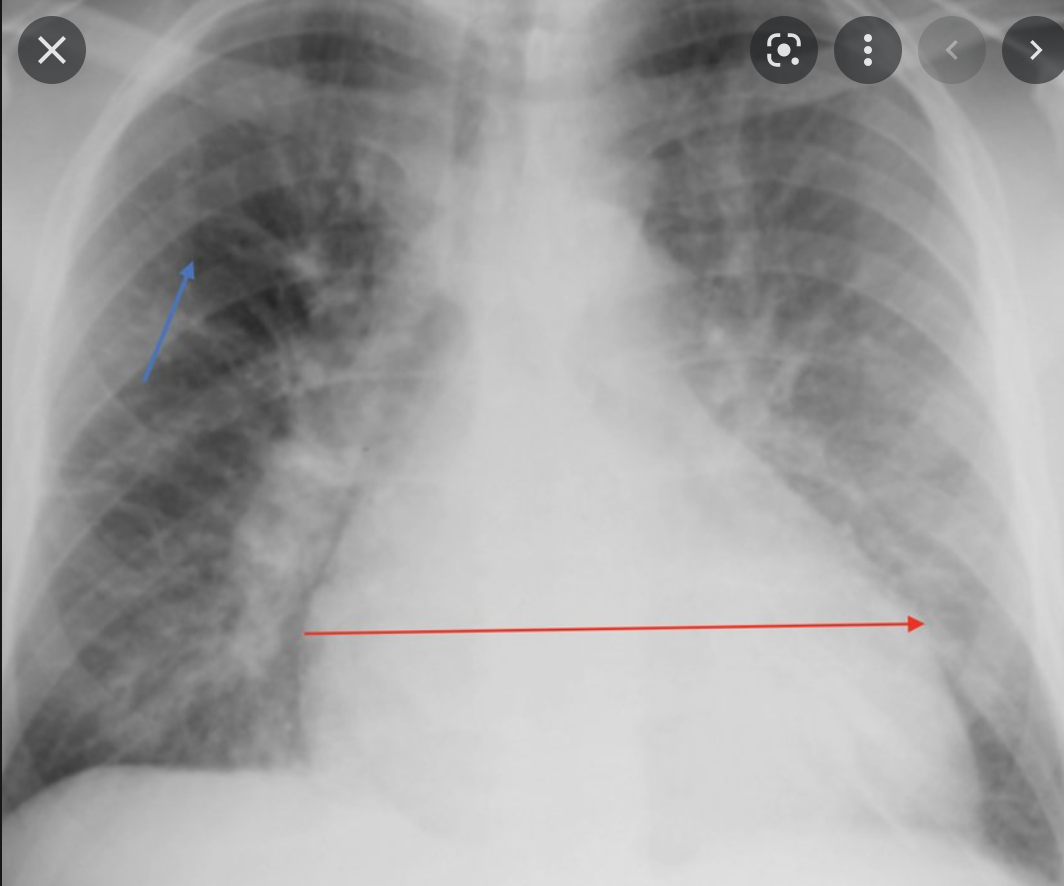

signs of pulmonary oedema of x-ray

A

• Bat wing sign

• Kerley B lines

heard failure on x-ray

Empyema – swing fever, complication of pneumonia Heart failure on x-ray * Cardiomegaly * Alveolar oedema * Kerley B